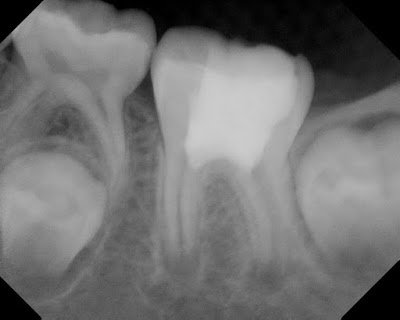

This 8 yr old presented in 2012 with deep caries on an immature #19. The pulp tested vital, but his dentist expected pulpal exposure. He was also reporting night time pain, which typically is associated with irreversible pulpitis.

Caries removed, pulp chamber cleaned out, MTA placed against the amputated pulp tissue, with resin restoration.